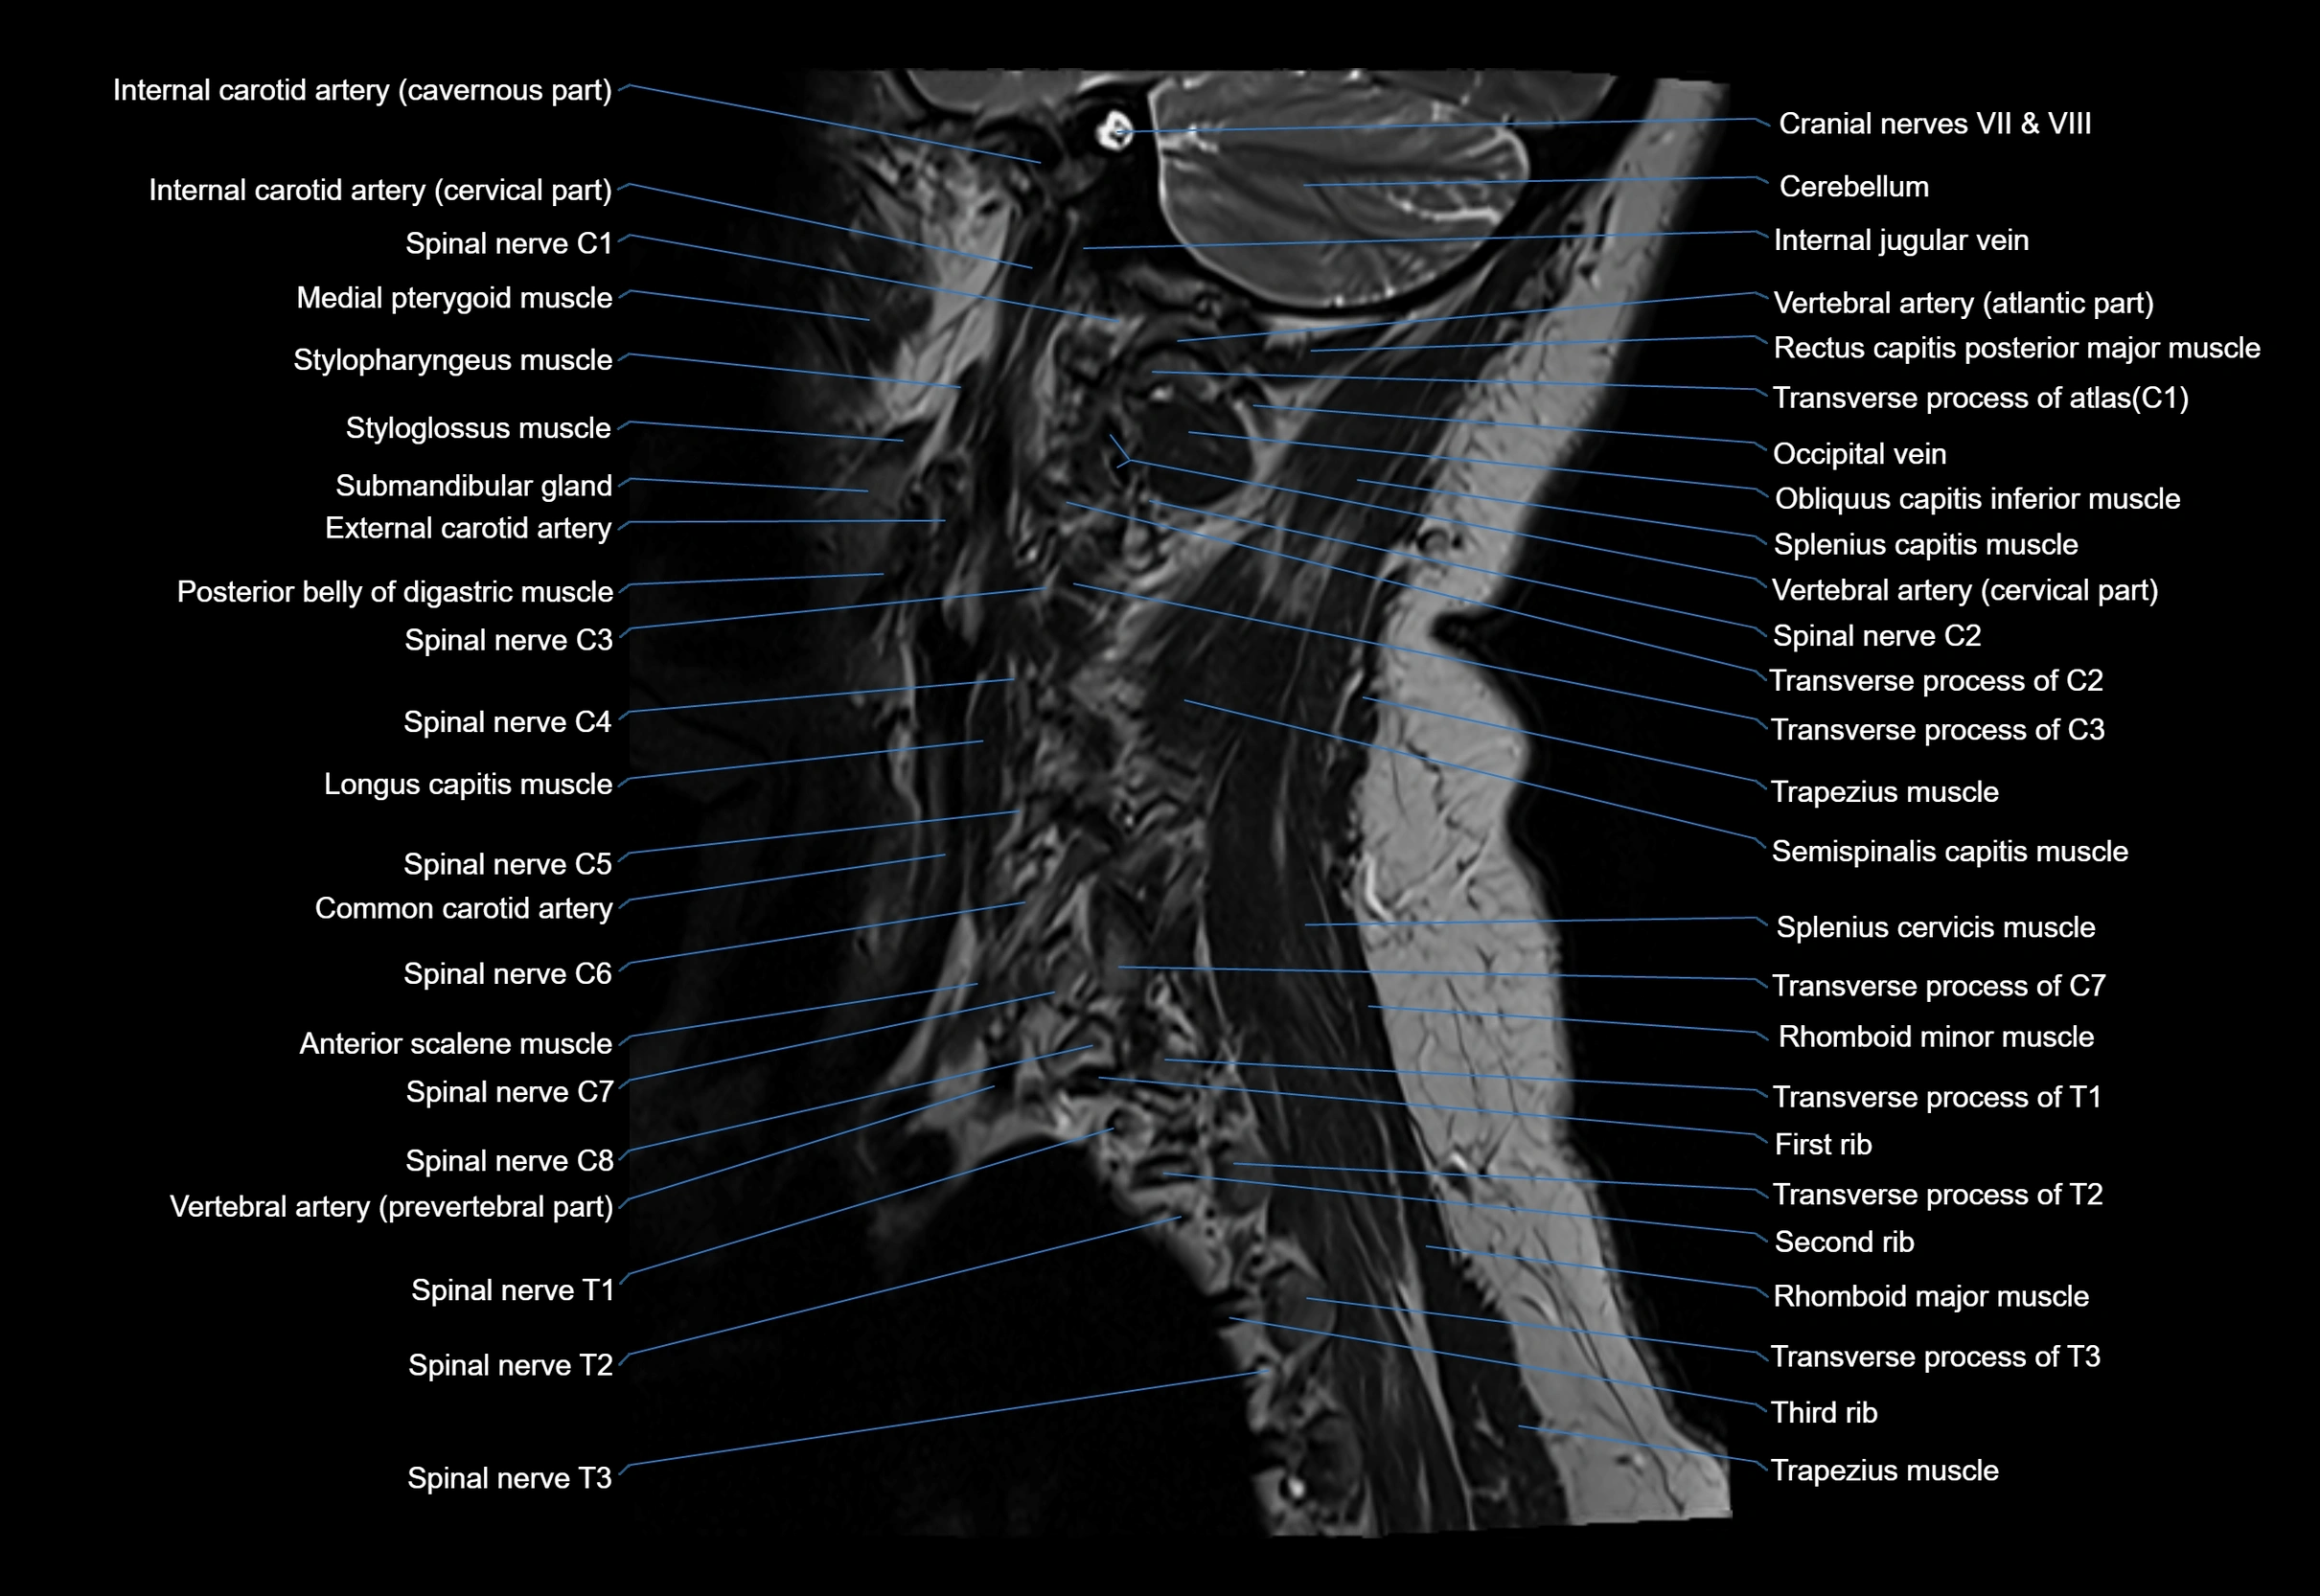

MRI image

image